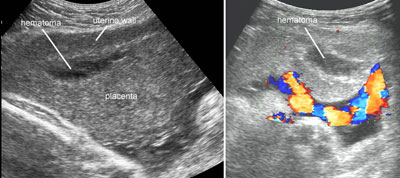

Abruptio placentae

Legend:Abruptio placentae